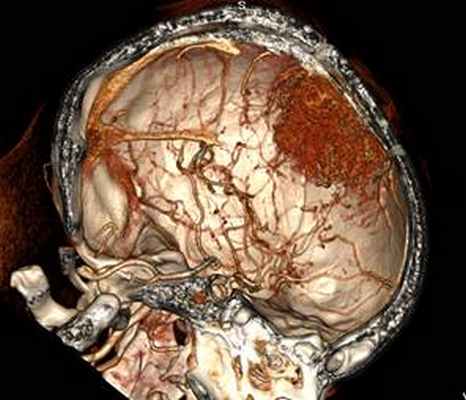

Опухоль обрастала переднюю мозговую артерию и перикаллезные артерии. После рассечения фалькса удалена опухоль с левой гемисферы, где опухоль также обрастала переднюю мозговую артерию слева, ее также удалось выделить и сохранить. Опухоль слева удалена. Осложнений во время операции не было. Гемостаз и закрытие раны проведены по общим принципам.

В положении больной на спине с учетом данных безрамной нейронавигации определена область доступа. Опухоль слева удалена тотально единым блоком после выделения опухоли по границе роста зоне. Кровотечений и осложнений во время операции не было. Гемостаз и закрытие раны проведены по общим принципам.